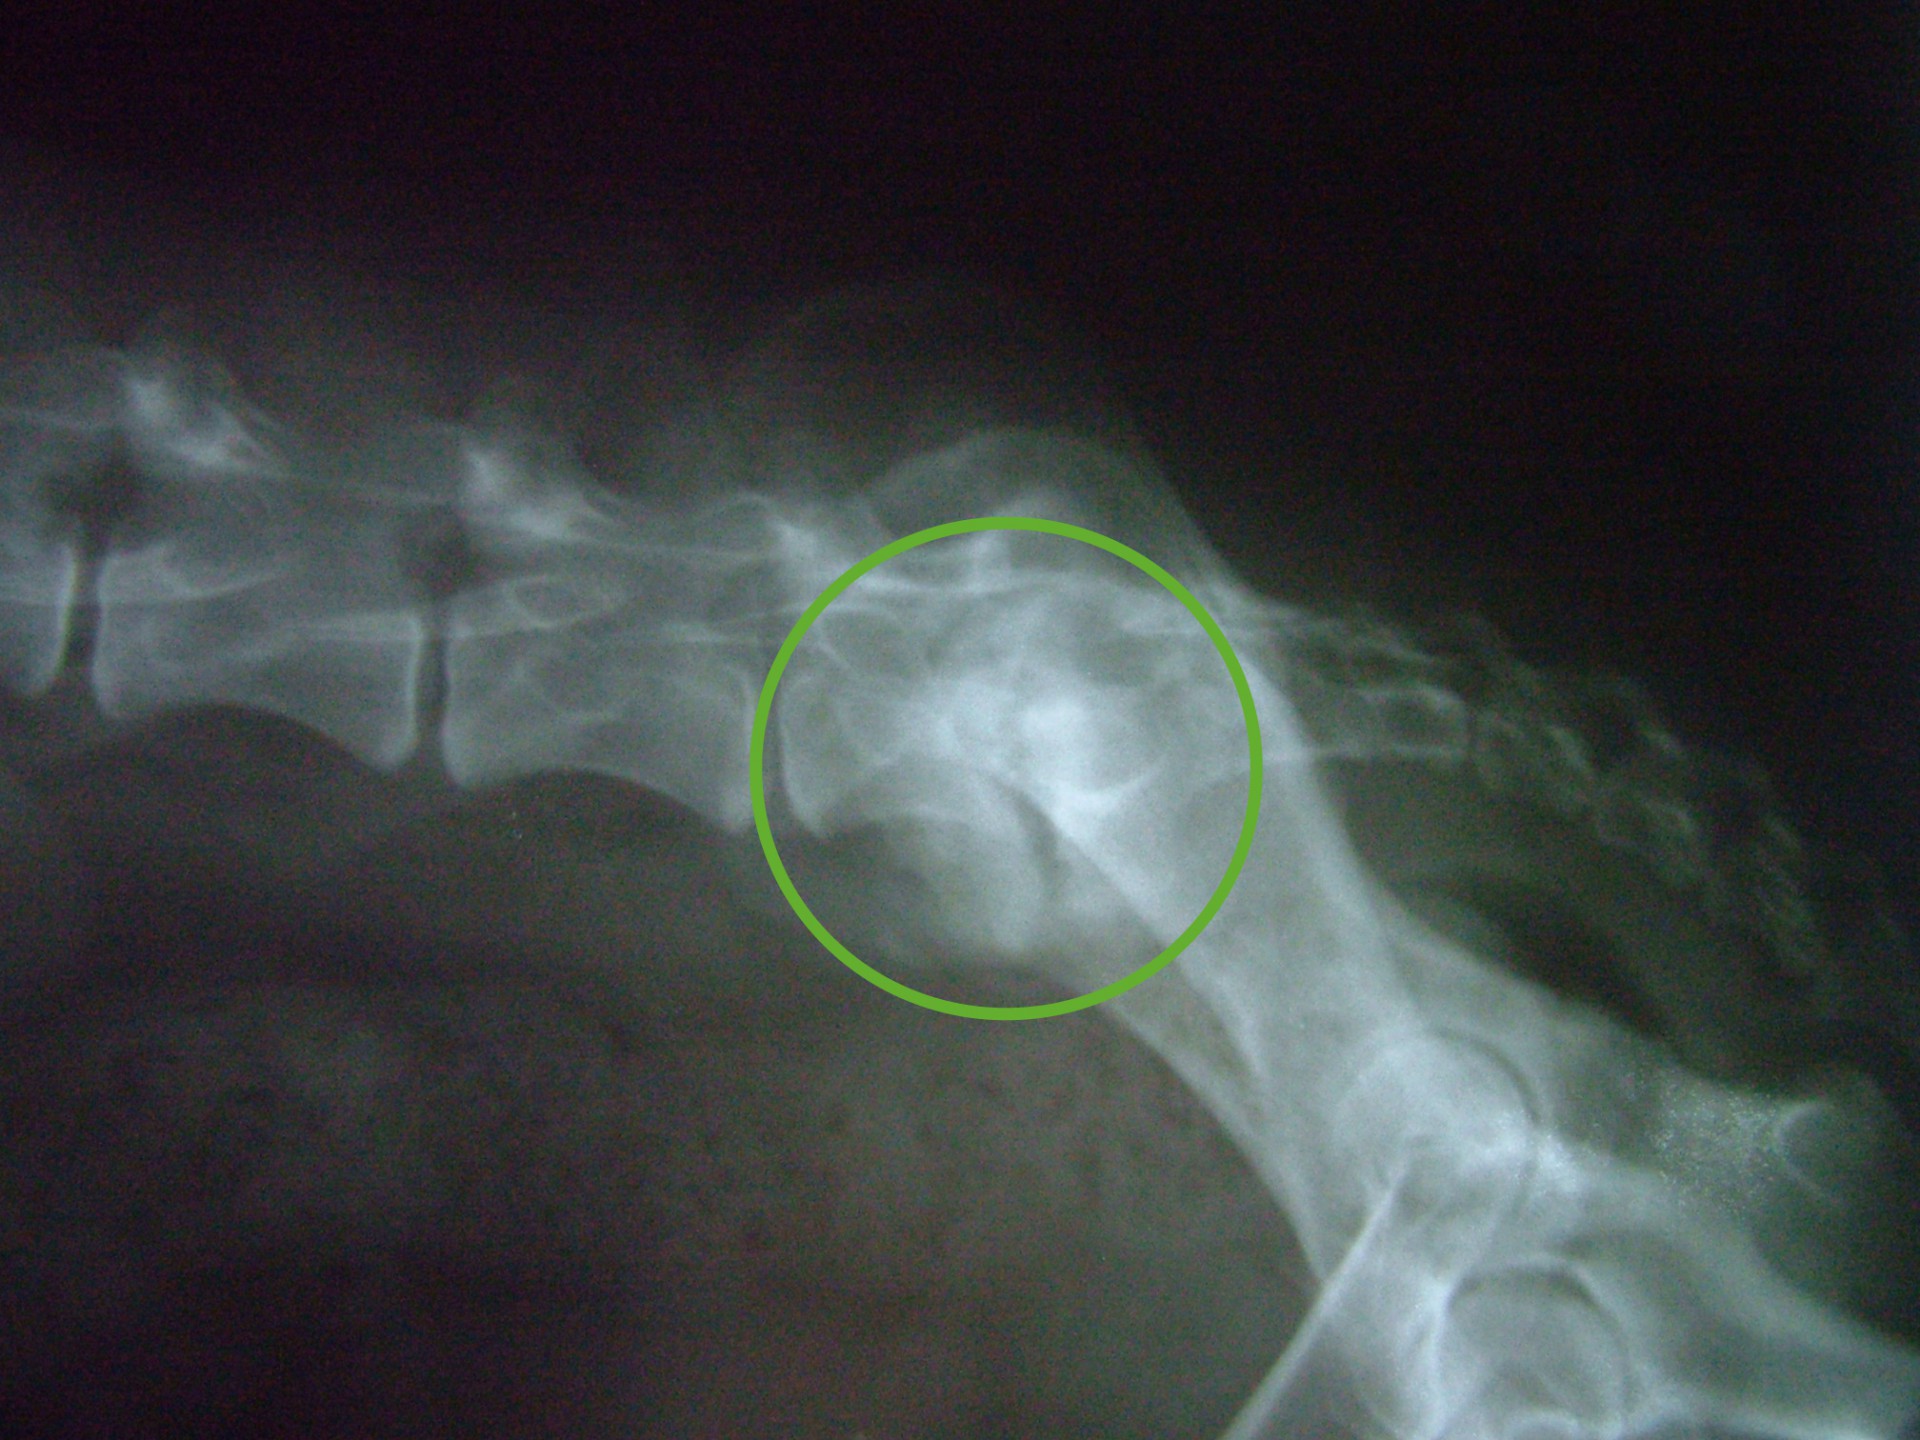

Szürke Farkas a 9 éves husky keverék kutya 4 napos csavargás után érkezett haza. Gazdája konstatálta, hogy a bal hátsó lábára sántít, így elhozta rendelőnkbe, ahol egy alapos vizsgálat után – mely során érdembeli elváltozást nem találtunk- fájdalomcsillapítókat adtunk neki és haza engedtük. Néhány nap után gazdája jelezte, hogy a kutya állapota nemhogy javulna, rosszabbodik. A kifejezett gerinctájéki fájdalmasság miatt myelographiát( gerincfestést) javasoltunk, mely során az utolsó ágyék és első keresztcsonti csigolya magasságában gerincvelő összenyomatást diagnosztizáltunk ( ld.: caudaequinacompressio). A sikeres műtétet követően néhány napon belül a fájdalom enyhült, együtt örültünk a gazdival.

Ám az öröm nem tartott sokáig. Szürke Farkas 5 nappal a műtéte után a kocsiba ugrás közben felsírt és mire a rendelőbe ért a fájdalomtól fel sem tudott állni. A kórházi felvételt követően fájdalomcsillapítók, antibiotikumok adását kezdtük meg és mivel a műtéti területen klinikai és RTG vizsgálattal sem találtunk a fájdalmat magyarázó elváltozást Kaposvárra, MRI vizsgálatra vittük. 2 nappal később meglepődve olvastuk az eredményt: a 9.-10.( Th9-Th10 ) hátcsigolyák valamint a 7 ágyéki és az 1. keresztcsonti csigolyák ( L7-S1 ) közötti porckorong gyulladásos elváltozása ( ld.: discospondylitis ) mellett a 11. és a 12. hátcsigolya magasságában ( Th 11-Th12 ) a gerincvelőt összenyomó daganatos elváltozás volt látható. Mivel a porckorongok gyulladása megmagyarázta a gerinctájéki fájdalmasságot, annak kezelése és a fájdalom további csillapítása volt az első teendőnk. Néhány nappal a fájdalom enyhülését követően a gerincvelőt összenyomó daganatot műtétileg eltávolítottuk. Ezt követően Szürke Farkas még további 60 napot töltött a kórházban. A lábadozása napról napra szépen alakult. Betegségének 90. napján hazaadtuk és a gyógyszerek további adása mellett állapotát hetente ellenőriztük.